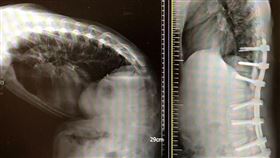

身高180突矮10公分⋯他背「有駝峰」醫驚

大陸一名男子近日發現駝背的情形越來越嚴重,背後像是有...

駝背男幾乎對摺 手術打開成壯漢險哭

中國南京一名男子,從小脊椎嚴重變形,越拖越嚴重,最終...